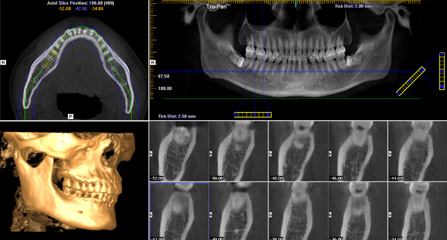

麦芽口腔着眼于全链条的数字化诊疗解决方案,与德国Kavo、瑞典Nobel、韩国奥齿泰、中国康泰健等国际知名齿科品牌合作,建立“深圳数字化口腔联盟”,应用全数字化口腔模式,从CBCT数据提取、AI口扫取模、AI智能口腔体检、数字化分析模拟与方案设计、3D打印、CAD/CAM椅旁加工以及手术模拟导航等,全流程打通数字化口腔精确诊疗的各个环节,实现麦芽数字化口腔诊疗体系新升级。

三维影像数据 一次性精确采集